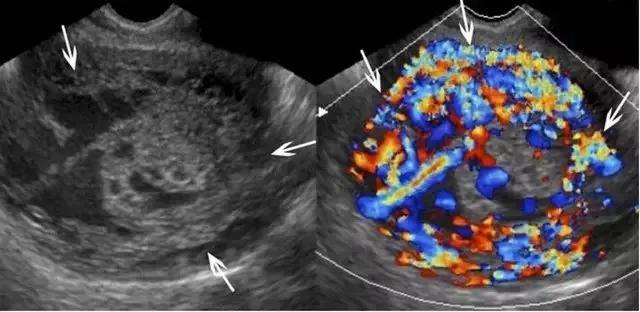

胎盘绒毛膜血管瘤是一种少见的具有胎儿血供的良性肿瘤,多位于胎盘的子面,居脐带进入胎盘处附近,可随着孕龄增加而增大。大于 5 cm 时,可导致羊水过多或过少、出血、早产、胎盘早剥、前置胎盘,胎儿非免疫性水肿,甚至胎儿窘迫或死亡,因而应经常对其进行超声随访。其表现是边界清晰的低回声包块,突出于胎盘表面,可能伴有钙化,表明瘤内血供减少及预后较好。瘤内如果测及高速动脉血流,则预示可能出现胎儿水肿(图 19)。

图 19 示胎盘绒毛膜血管瘤:A 为孕 35 周的胎盘绒毛膜板附近的低回声包块(长箭头),内见微小钙化(短箭头)。B 为 A 的彩色血流图,可见一支血管向肿块供血(箭头),星号指示肿块内的血供情况。孕妇无异常表现,足月生产一正常胎儿,胎盘的组织学检查证实为绒毛膜血管瘤